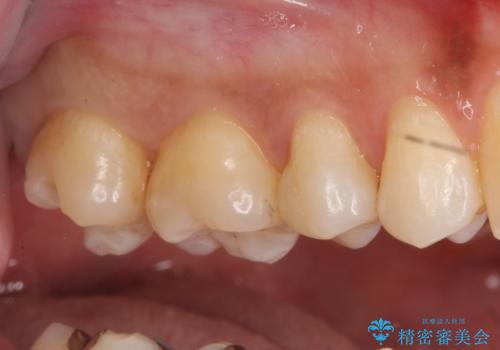

奥歯の虫歯 セラミックインレーに

- 上の奥の虫歯をセラミックインレーで修復しました。

奥歯は力がかかるところであるので、保険適応の白い材料は必ず劣化し、2次う蝕(再度虫歯)になる可能性が非常に高いですので全くおすすめできません。

2次う蝕になり、治療を繰り返していると抜髄(神経を取らないといけない)の可能性が高まります。

特に自費のインレーの適合(歯にぴったり合っている)はとても良く、虫歯になりにくいです。